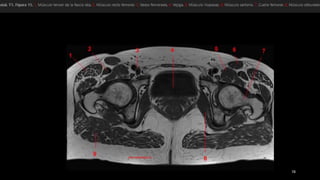

• tensor de la fascia lata (tfi), el psoasilíaco

(Ips), el sartorio (sa) y el recto femoral (rf).

• los vientres musculares se representan en

gris y los tendones, en negro.

• Punta de flecha blanca señala el tendón del

recto femoral.

• flecha, fascia lata.

• músculos pectíneo

(Pt), aductor largo (1),

aductor corto (2),

aductor mayor (3) y

recto interno (Gr).

• ObtE, obturador

• tensor dela fascia lata (tfi), el psoasilíaco (Ips), el sartorio (sa) y el recto femoral (rf). • los vientres musculares se representan en gris y los tendones, en negro. • Punta de flecha blanca señala el tendón del recto femoral. • flecha, fascia lata.

• músculos pectíneo (Pt),aductor largo (1), aductor corto (2), aductor mayor (3) y recto interno (Gr). • ObtE, obturador externo

• #60  Características anatómicas de los músculos y tendones de la región anterior (flexo res) de la cadera. Conjunto de dibujos (a,c,e,g) e imágenes de RM potenciadas en T1, correspondientes, (b,d,f,h) que ilustran las relaciones entre el tensor de la fascia lata (TfI), el psoasilíaco (/Ps), el sartorio (Sa) y el recto femoral (RF) en los pIanos transversales, obtenidas de proximal a distal. Los vientres musculares se representan en gris y los tendones, en negro. En a,b), la punta de flecha blanca señala el tendón del recto femoral. Obsérvese que el músculo sartorio cruza por encima del psoasilíaco de lateral a medial en su trayecto descendente. Flecha, fascia lata.

• #61  Características anatómicas de los músculos y tendones de la región interna (aductores) de la cadera. a) Dibujo de una vista anterior de la cadera y b) imagen transversal de RM potenciada en T1, correspondiente, que ilustran las relaciones entre los músculos pectíneo (Pt), aductor largo (1), aductor corto (2), aductor mayor (3) y recto interno (Gr). Obsérvese la disposición en capas de los músculos aductores, donde el aductor largo es el más superficial y el aductor mayor, el más profundo. ObtE, obturador externo.